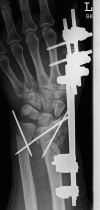

Diatal radius fractures (DRFs) are typical fractures of relatively fit persons with osteoporotic bone who remain active into older age. Traditionally, DRFs in older patients have been treated with closed reduction and cast immobilization. Considering the increasing life expectancy of the elderly population, appropriate management of these fractures is of growing importance. Decision making for surgical or nonsurgical approach to osteoporotic DRFs is difficult. These decisions are often made based on the data from treatments of much younger patients. The current literature concerning the treatment of DRFs in the elderly individuals is more controversial. Some investigators have recommended open reduction internal fixation (ORIF) as treatment for unstable DRFs in older patients, while others have suggested that elderly patients should be treated nonsurgically even if there is an unstable fracture situation because fracture reduction is not associated with functional outcomes as in younger patients. This article reviews the different treatment options for DRFs in the elderly individuals reported in the recent literature.